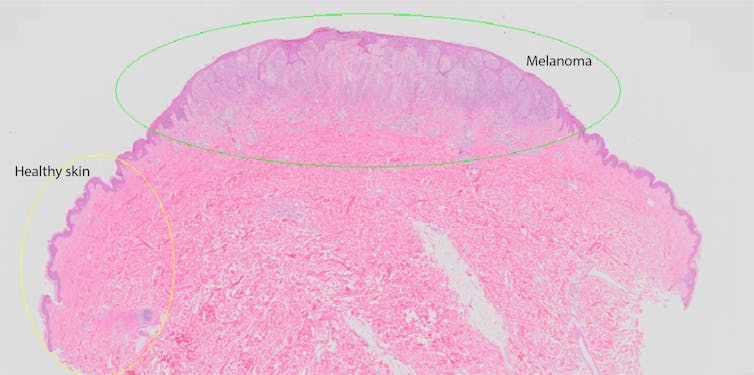

After the initial excision of the melanoma, it’s sent to a pathologist to be examined under a microscope. They will generate a report describing the melanoma in detail to help your doctor know what to do next.

The most important detail is the thickness of the melanoma from the skin surface to its deepest edge. In situ melanomas are so thin they have no official measurement, and invasive melanomas are measured in millimetres. Over 1mm thick is where your doctor will start to be much more concerned about the risk of spread.